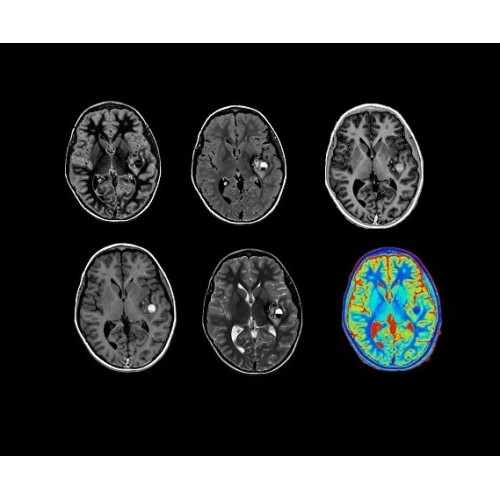

SIGNA PET/MR 3.0T — это гибридная система, в которой совмещаются две принципиально разные технологии — магнитно-резонансную томографию (МРТ) и позитронно-эмиссионную томографию (ПЭТ). Система отличающийся высокой чувствительностью и эффективностью и предназначена для диагностики в области онкологии, неврологии, кардио-васкулярных исследований, исследований воспалительных процессов.

Компания GE Healthcare представляет революционную, полностью интегрированную систему SIGNA PET/MR1, в которой сочетаются времяпролетная технология (TOF) и возможности напряженности магнитного поля 3.0 Тл. Мы поможем вам поднять исследования на более высокий уровень. SIGNA PET/MR позволяет достичь впечатляющей точности и скорости исследований, а благодаря новейшей технологии реконструкции Q.Clear2 качество изображений улучшается в два раза. Кроме того, в систему включен полный набор клинических приложений и гибких катушек для проведения любых видов исследования, открывая для вас возможности визуализации, о которых вы даже не догадывались.

Кроме того, в результате использования технологии TOF и инновационной технологии реконструкции Q.Clear вы сможете добиться прекрасного соотношения сигнал/шум. А благодаря технологии нулевого времени эхо (ZTE) визуализировать костную структуру без ионизирующего излучения. Все эти разработки для улучшения качества сканирования и точности анализа помогут вам использовать весь потенциал ПЭТ/МРТ.

Система SIGNA PET/MR предлагает впечатляющие клинические возможности и открывает доступ к наиболее полным пакетам программных приложений.

• Q.Clear — в основу технологии легли накопленные знания о том, как минимизировать помехи при реконструкции и получить четкое изображение. При значительном улучшении качества изображения сохраняется точность расчетов. Сочетание технологии TOF и реконструкции Q.Clear — ваш надежный помощник для получения точных и достоверных данных.

• МРТ с функцией нулевого времени эхо (ZTE) отличается точностью, возможностью персональных настроек и отсутствием ионизирующего излучения. Она приходит на смену традиционному исследованию на основе рентгеновского излучения. МРТ с функцией нулевого времени эхо (ZTE) на базе SIGNA ПЭТ/МРТ является более надежной и быстрой по сравнению с системами, использующими сверхмалое время эхо (UTE).

• Специальный пакет приложений для измерения и сравнения объемных изображений ЦНС с нормами поможет вам в диагностике нейродегенеративных заболеваний, а дополнительные инструменты визуализации — в постановке точного диагноза с помощью бета-амилоидов и радиоизотопных маркеров ФДГ.